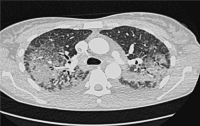

Abbildung 2: Ausgedehnte beidseitige Infiltrate und Milchglasareale bei einer Salazopyrin-getriggerten akuten eosinophilen Pneumonie (siehe Kasuistik 2).

Keywords:

CT

,

eosinophile Pneumonie

Eosinophilie

Thorax